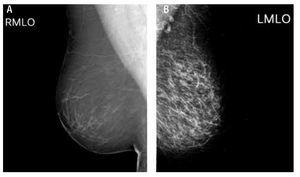

Una imagen de alta calidad es aquella que muestra alto contraste entre las estructuras del tejido a estudiar, alta resolución espacial, bajo ruido y baja dosis de radiación (Figura 1). Para obtener imágenes de alta calidad se han diseñado equipos y técnicas especiales para tal fin, en mamografía se ha diseñado el mastógrafo para obtener dichas imágenes.

Figura 1.Mamografía. A) Imagen de alta calidad. La imagen fue obtenida con parámetros adecuados, con un posicionamiento correcto y no muestra artefactos. B) Imagen de baja calidad. La imagen fue obtenida con parámetros incorrectos de exposición, el posicionamiento no es correcto y se observan artefactos debidos a suciedad en el chasis y rejilla antidispersora.